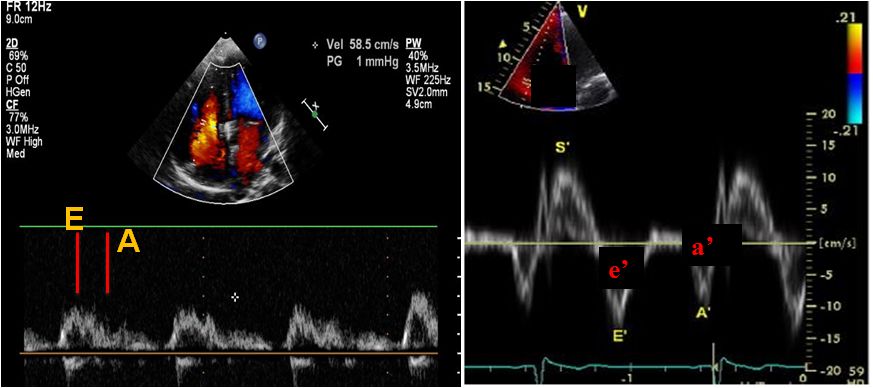

二尖瓣口舒张期血流频谱E峰、A峰、E/A比值及Valsava动作E/A 比值变化(Val. ΔE/A)

二尖瓣口E峰减速时间—DT、等容舒张时间—IVRT

舒张早(晚)期二尖瓣环运动速度e’(a’)、E/e’比值

➤ 评估左室舒张功能四个简化指标

二尖瓣环e’(间隔e’< 7 cm/s,侧壁e’ <10 cm/s)

平均E/e’ > 14

左房最大容积指数> 34 mL/m2

TR峰值流速> 2.8 m/s

简单,特异性高,降低假阳性率

J Am Soc Echocardiogr.2016;29:277-314.

➤ 三尖瓣口血流脉冲多普勒与瓣环组织多普勒

1.舒张期三尖瓣E峰减速时间及E/A比值;

2.三尖瓣环侧壁侧舒张早、晚期峰值速度(e’ 、e’ /a’及E/ e’);